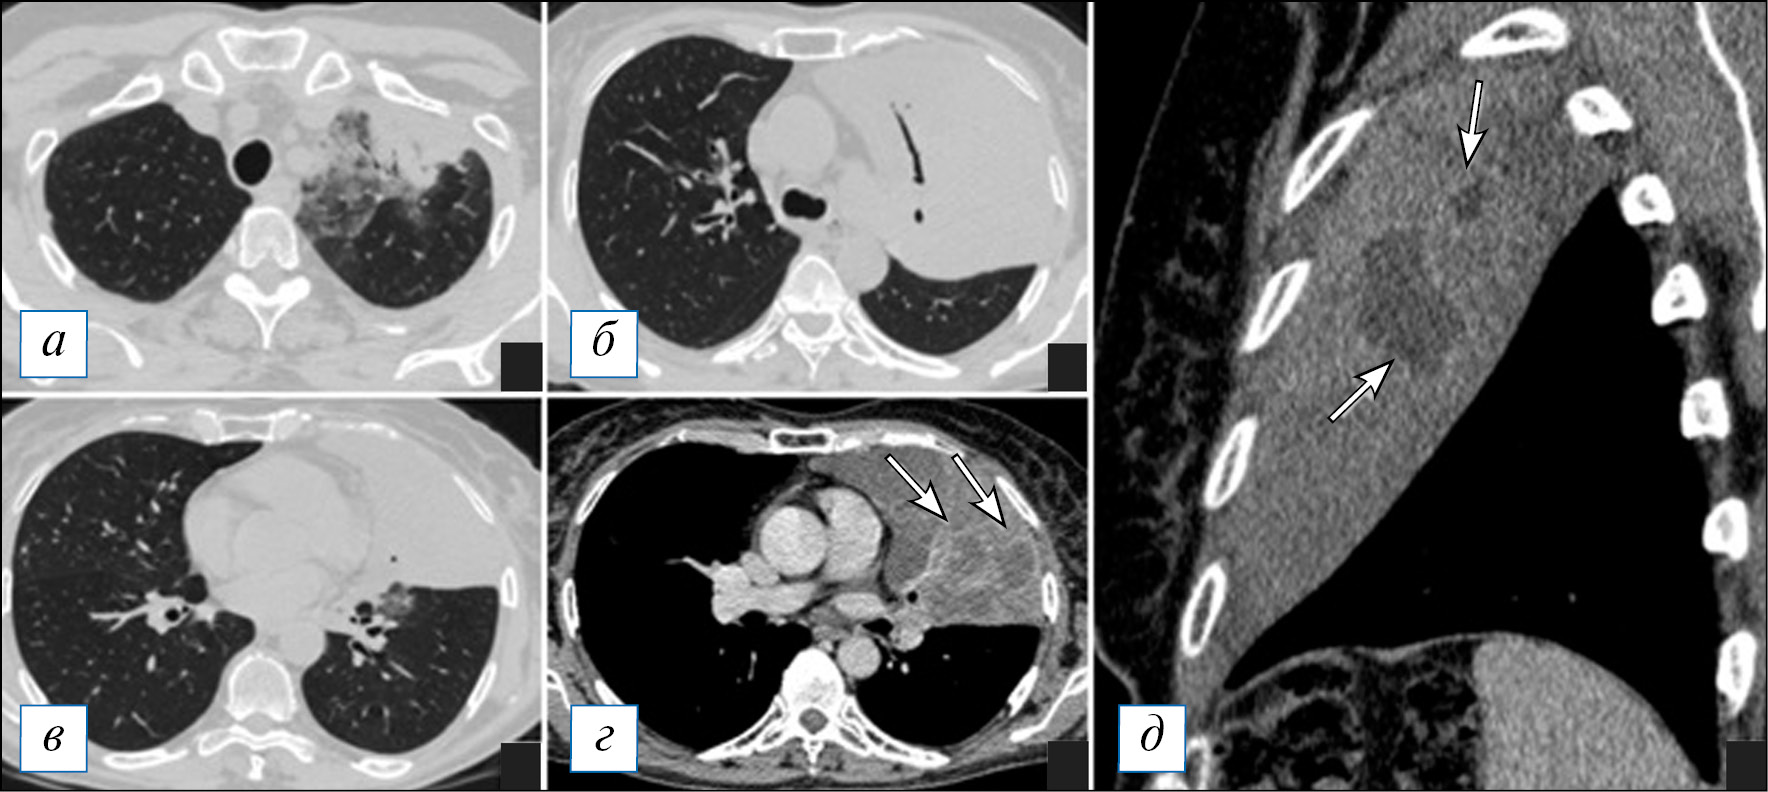

При проведении КТ органов грудной клетки отмечается уплотнение, чаще в виде консолидации или по смешанному типу, в сочетании с «матовым стеклом» пораженной части легкого, которая может быть несколько увеличена в размерах (рис. 2, Б), что объясняется скоплением экссудата и отеком легочной паренхимы по типу «выбухающей борозды». На фоне уплотнения быстро происходит деструкция легочной ткани в виде множественных очагов или более обширных участков; в начале этого процесса в полостях распада можно наблюдать некоторое количество содержимого с горизонтальным уровнем; секвестры нехарактерны (рис. 2). Внутренняя стенка полостей имеет четкий контур, что объясняется дренированием содержимого через бронхи, которые в ряде случаев прослеживаются (рис. 3). Может отмечаться выраженная реакция плевры, с развитием выпота или даже эмпиемы и пиопневмоторакса, особенно при формировании свища [8, 9, 40]. Негативными последствиями некротизирующей пневмонии может являться формирование фиброза с бронхоэктазами, персистирование полостей распада при отсутствии их спадения, а также облитерация плевральной полости на уровне воспалительного процесса [39].

Рис. 2. Компьютерная томография органов грудной клетки в аксиальной проекции (а–г). Двусторонняя полисегментарная пневмония. С обеих сторон в легких, больше справа, имеются инфильтраты, на фоне которых просматриваются полости различного размера без жидкостного содержимого. Незначительный пневмомедиастинум. [Изображения из архива авторов]. / Fig. 2. Chest CT, axial projection (а–г). Bilateral polysegmental pneumonia. On both sides in the lungs, more to the right, there are infiltrates and cavities of various sizes without liquid content. Minor pneumomediastinum. [Images from the authors’ archive].

Рис. 3. Компьютерная томография органов грудной клетки в аксиальной проекции (а, б). Пневмоническая инфильтрация в верхней доле слева с деструкциями. Имеются участки по типу «шальной исчерченности» в сочетании с консолидацией, на фоне которой обнаруживаются разнокалиберные полости распада без содержимого, наружный их контур не прослеживается. [Изображения из архива авторов]. / Fig. 3. Chest CT, axial projection (а, б). Pneumonic infiltration in the upper lobe on the left with destructions. There are areas of a «crazy paving» sign in combination with consolidation, against the background of which one can see destructive cavities of various sizes without content, their outer contour is not traced. [Images from the authors’ archive].